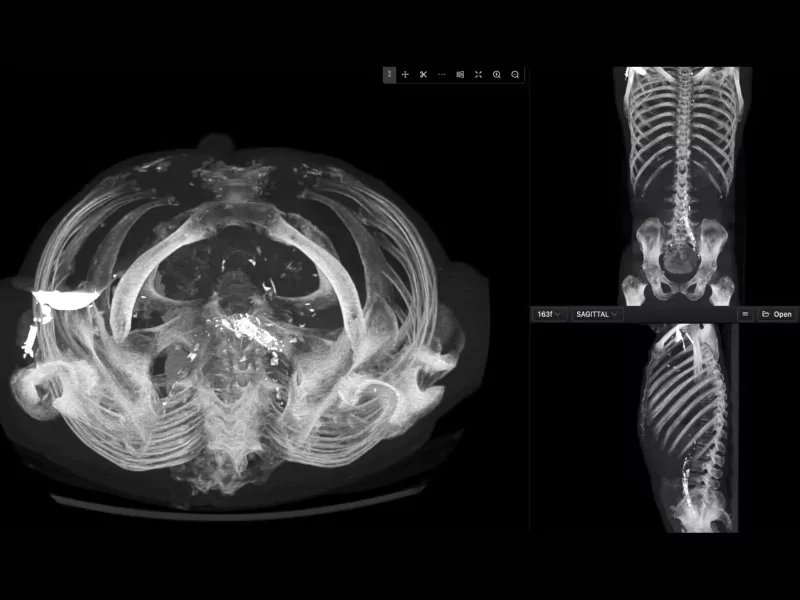

Images from CT scans or X-rays are often unclear, or it is difficult to identify any irregularities. Radiology image labeling can locate and mark these irregularities for doctors. Image tagging helps to identify any illness or damage within a body.

In radiology results, bones and muscles were not marked with their names and size. Image marking sends information to AI to identify different types of bones and muscles in a body. In this way, any dislocation or sprain can be identified.

MRI uses AI-assisted radiology annotation to tag chest, abdominal, pelvic, and vertebrae areas. It has been seen that any problems detected in the human body can be identified by annotation in MRI. Radiology image analysis gives an overview of the infection in the MRI results.

We provide polygon annotation services that can help you tag an infection’s irregular shapes. In image segmentation, these markings will show you the exact diameter of the infection on a CT scan or MRI plate.

It gets difficult to pinpoint specific areas in CT scans or MRIs. With semantic segmentation, you can annotate the whole image of the plate. In this way, you can separate the diseased portions from the healthy ones in the human body.